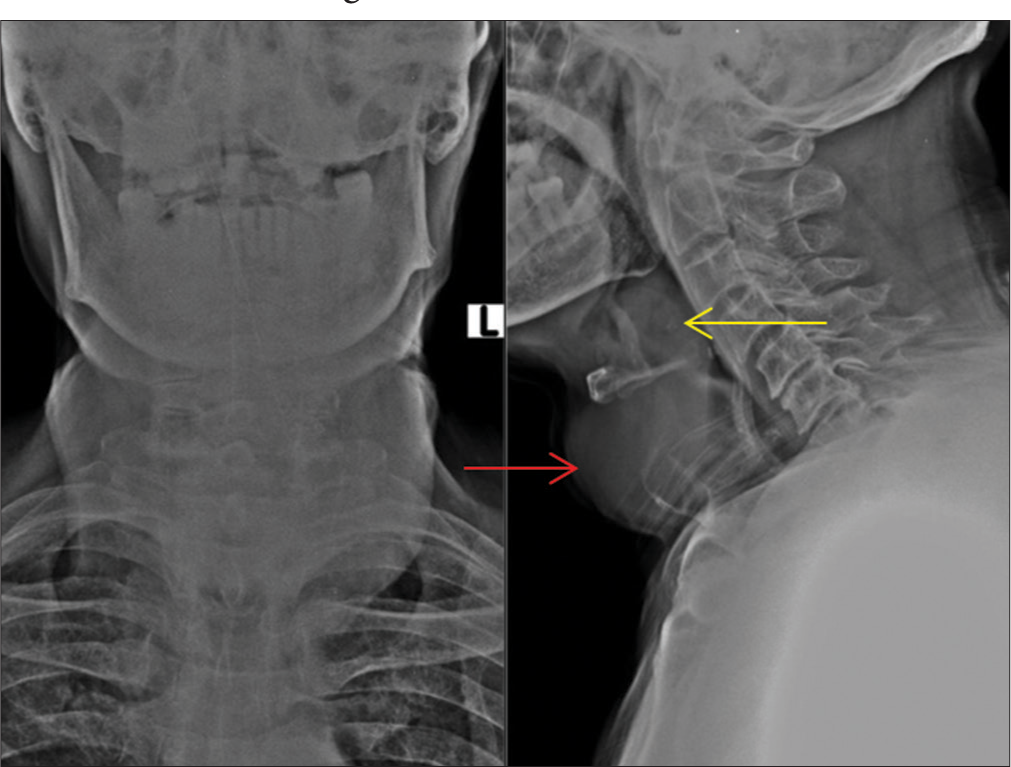

Manodoss Nancy, T. Mukuntharajan, N. Karunakaran, Ganesh Rajagopal, S. Shanmuga Jayanthan, K. Nadanasadharam, Gowtham Ramasamy